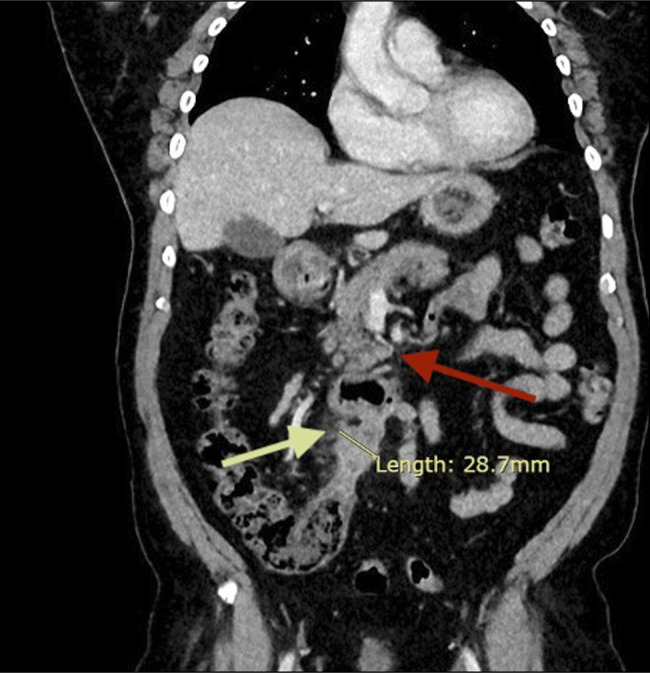

Vermiform appendiceal cancers are rare and commonly diagnosed incidentally after appendectomy for acute appendicitis. Establishing a diagnosis and staging appendiceal cancer is important as the treatment options differ based on the subtypes of tumor and their spread in the peritoneum. The role of endosonography in tissue diagnosis of appendiceal cancer is limited. Most cases are diagnosed and staged radiologically and surgically. Tissue diagnosis is key in management, especially when diagnosis is unclear by other modalities. We report a case of transduodenal endoscopic ultrasound-guided biopsy of an appendiceal lesion, which had significant impact on patient outcome.